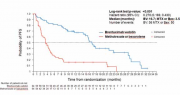

| 15:32, 21 בנובמבר 2017 | CLL-2.png (קובץ) |  |

510 קילו־בייטים | Motyk | 1 | |